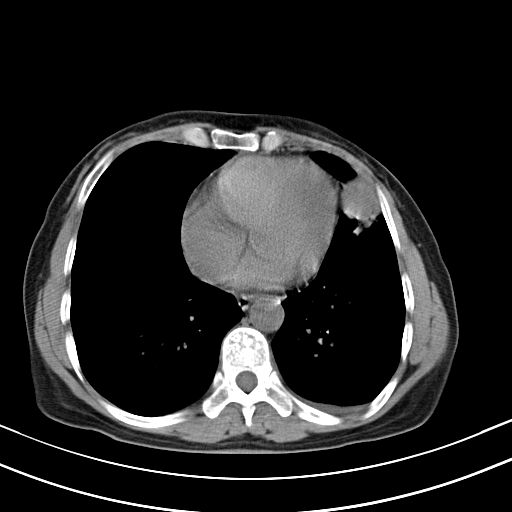

女,47岁,咳嗽胸痛一个星期,我们考虑肺结核,左下肺病灶肿瘤像不像,请高手指点。急。

右肺考虑炎症,建议抗炎后复查,左肺下叶考虑肺不张。

炎性灶;【1楔状实变影,有支气管气象,2近端纹理影增重】

右肺上叶前段积左肺舌叶炎症,建议严格抗炎后2周复查!

右肺上叶尖后段班片影不能出外肺结核。左肺舌叶三角形实变影,增强明显。考虑炎性病变

考虑两肺炎症,左胸腔积液,建议治疗后复查!

考虑炎性病变,左肺舌叶病灶需要与早期肺脓肿鉴别(结合实验室),左侧少量胸腔积液。

右肺为炎性改变,左肺病灶影像所见1、楔状实变影,边缘呈刀切样,见支气管气象,2、近端纹理影增重。

并从一元化来解释,还是符合炎性病灶。建议抗炎后复查。

两肺病变考虑炎症可能性大。(左肺病变呈楔状实变影,有支气管气象,近端纹理影增重)。

1)右肺上叶前段及左肺上叶舌段感染性病变;建议抗炎治疗后复查。2)左侧少量胸腔积液。

考虑右肺上叶前段及左肺舌叶炎症,建议抗炎治疗后复查除外结核。

左肺舌叶病灶呈扇形分布,其内可见支气管影,胸膜面光滑,不支持肿瘤病变。